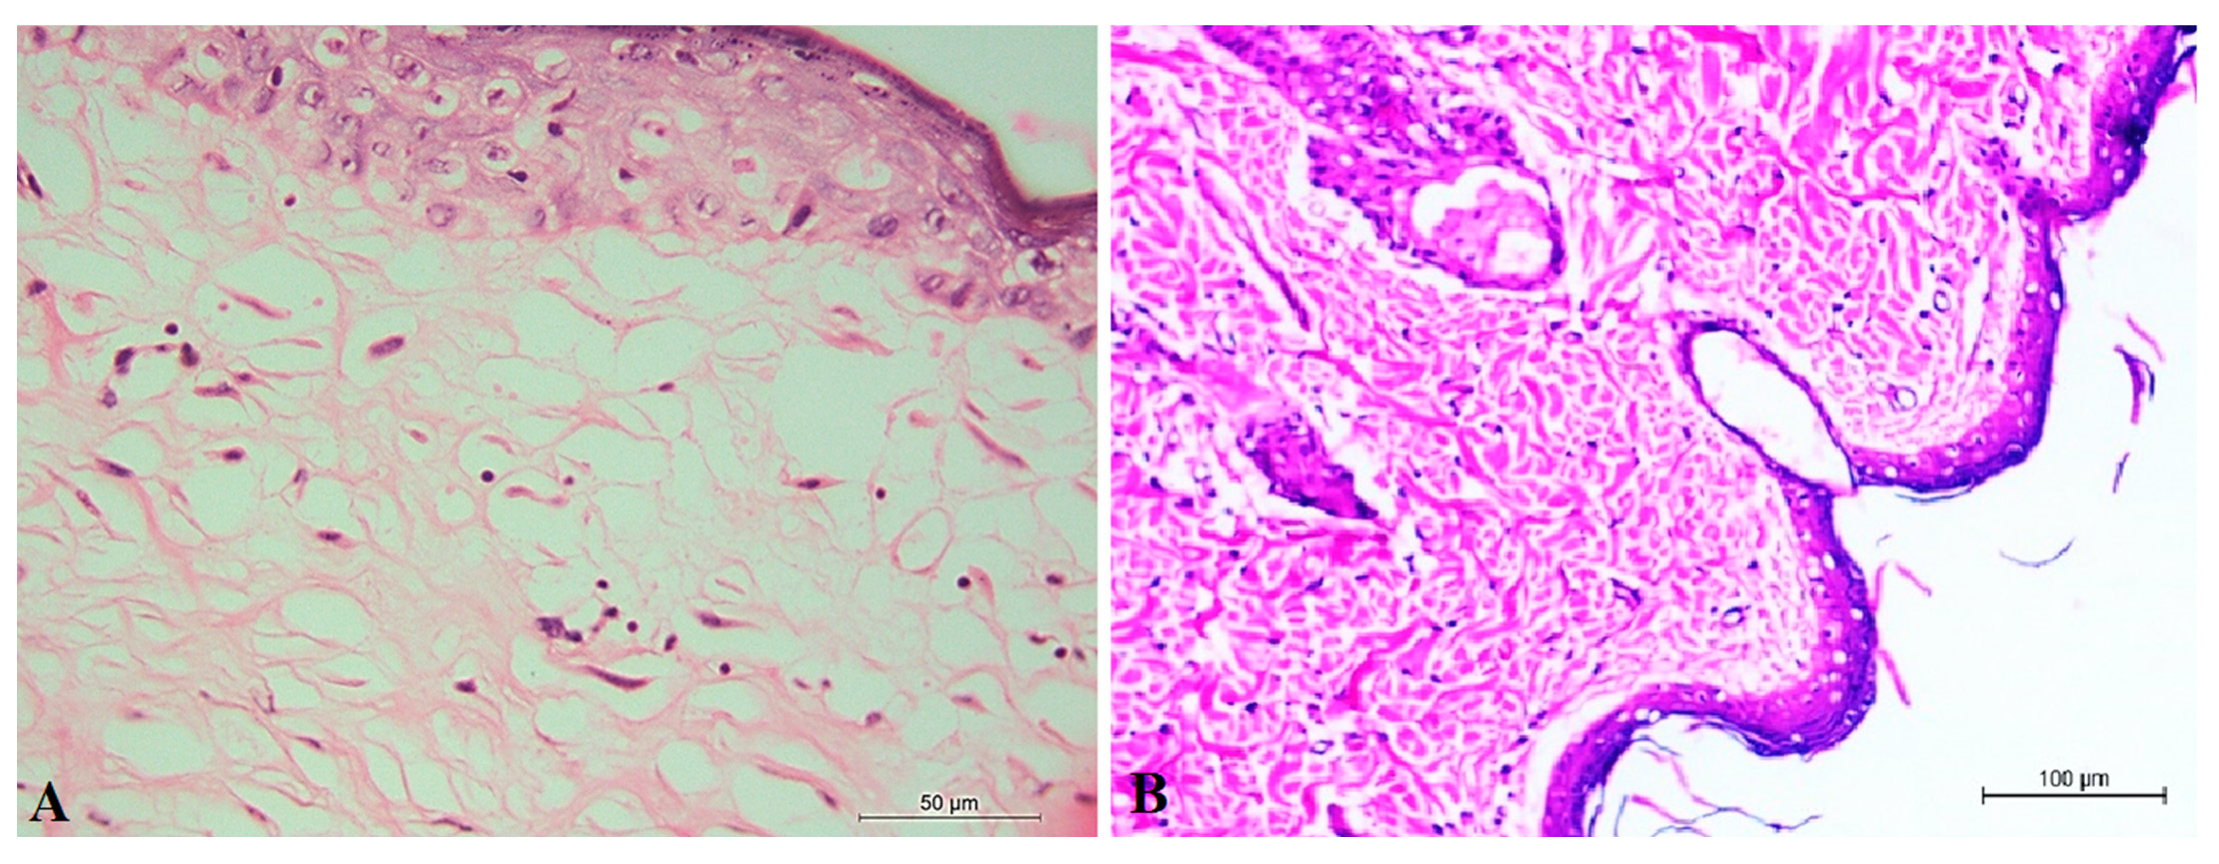

3.4.4. Histopathological Examination of Optimum ALN Gel Formulation